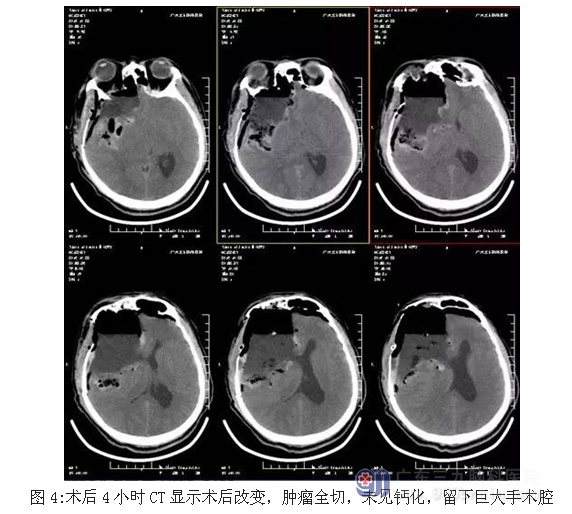

患者江某某,男性,39岁,发热后头部胀痛,当地医院就诊,CT显示:颅内巨大占位性病变,为求有效治疗,来我院就诊。入院后完善术前相关检查,术前CT显示大片状、点状钙化高密度影,术前CTA检查示:右侧额颞叶巨大高低混杂密度影,术前磁共振显示肿瘤位置及大小约10.8×8.6×8.7cm,完善术前准备后,行全麻下右侧额颞岛叶-基底节肿瘤切除术,手术由神经外一科主任张良主刀完成,术中肿瘤全切,术后恢复良好。

少突胶质细胞瘤以手术治疗为主,术后平均生存期为3-5年,辅以放疗和(或) 化疗, 以防肿瘤复发或者残存肿瘤增大。本例患者为WHO II级,低度恶性,术后肿瘤全切,予以继续行放疗,目前进一步随访中。